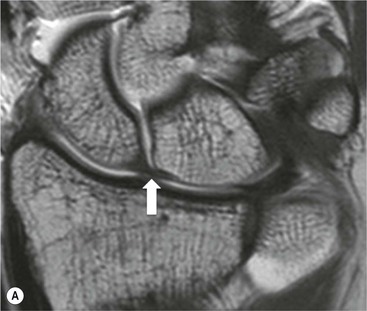

The scapholunate ligament is most frequently involved. Radiographs may show scapholunate diastasis (>3 mm). The lunate demonstrates dorsal rotation on lateral views and volar rotation of the scaphoid. This results in an increase in the scapholunate angle (>60°) known as dorsal intercalated segment instability (DISI) (Fig. 46-27). A DISI deformity of the carpus may also be associated with fractures of the scaphoid.

Abnormal communication between the radiocarpal and midcarpal joints may be seen on arthrography (Fig. 46-28), which is usually combined with MRI or CT16 (Figs. 46-29 and 46-30). However, direct visualisation of the ligaments is possible with conventional MRI. The most important features to describe that help determine management include the following: